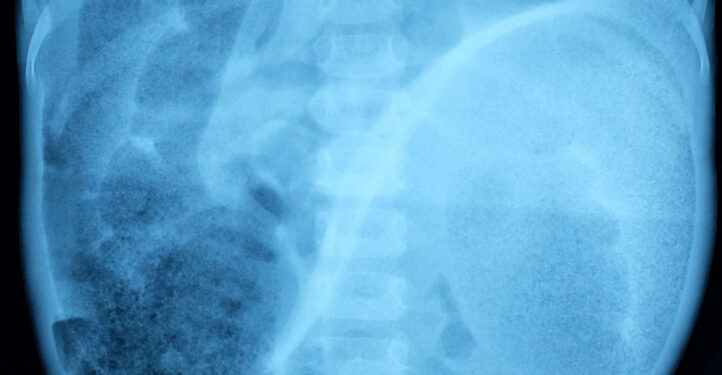

- Pilvo rentgenograma – leidžia pamatyti, ar neatsirado žarnų nepraeinamumas.

- Kontrastinė klizma – į tiesiąją žarną per judrų vamzdelį suleidžiamas specialus skystis, padedantis rentgenu pamatyti žarnos sienelių struktūrą ir galimus susiaurėjimus ar užsikimšimus.